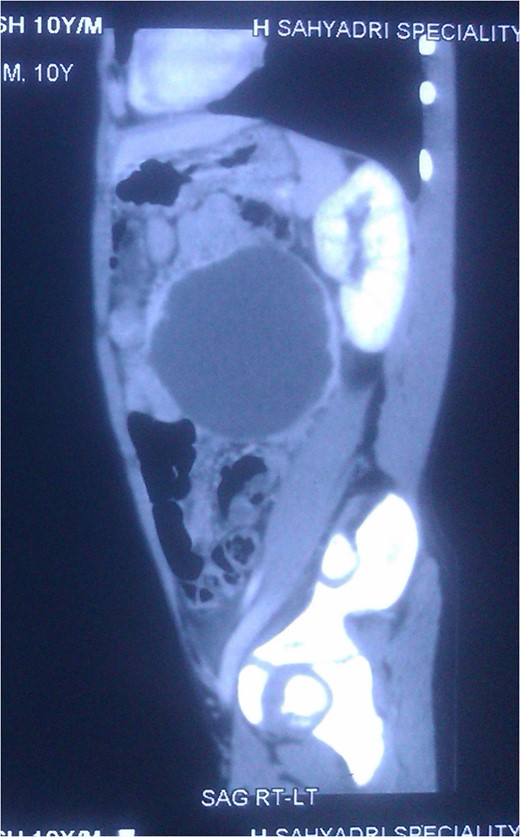

Hemoglobin, leucocyte and platelet counts were normal. Ultrasonography revealed a large hypoechoic cystic lesion involving the spleen measuring 108 × 98 mm with thin internal septa. CT scan—A large well-defined cystic lesion with few thin enhancing septa within it is seen involving the spleen. The lesion is causing mass effect and displacing adjacent vessels and bowel loops (Figs 1, 2).

CT Scan: Cross section showing the splenic mass almost reaching the midline.